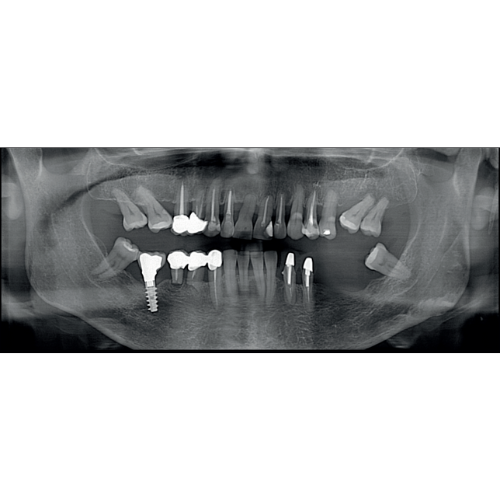

X-MIND® optima 3D represents the perfect combination of advanced hardware technology, enclosed in a lightweight and compact design and next-generation software, RealGuide™ 5.4, bringing the benefits of Artificial Intelligence into every step of patient care, from a precise diagnosis to more effective treatments and patient communication.

- 2D and 3D Imaging

- Panoramic